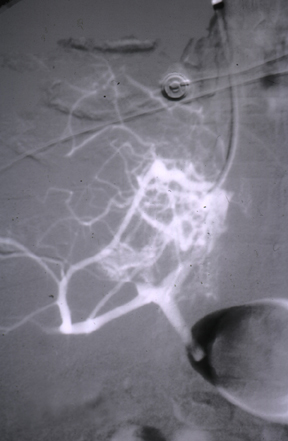

| The hepatic venogram at the left reveals lack of filling in the venous outflow due to hepatic venous thrombosis with Budd-Chiari syndrome. In the venogram at the right, there is a central dark area from thrombosis in the inferior vena cava that extended from the hepatic veins. The Budd-Chiari syndrome can result from polycythemia vera, pregnancy, and carcinomas in the abdominal region. |